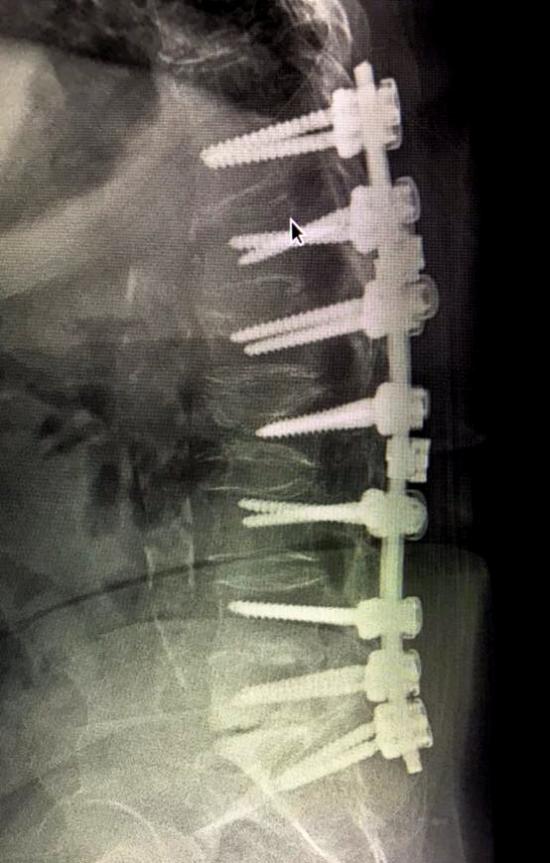

REBORN SPINAL STABILIZATION SYSTEM

Spinal Stabilization System Reborn ® Spinal Fixation System is an implant system used to treat a r...